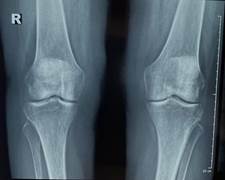

При осмотре обращала на себя внимание дефигурация левого коленного сустава, ПМФС кистей, правого голеностопного сустава за счет экссудативных проявлений, множественные тофусы периартикулярных тканей (Рис.1). Болевой синдром по ВАШ 65-70 мм.

/Sinenko.files/image001.jpg)

а,б

/Sinenko.files/image003.jpg)

в

Рисунок 1. Изменения верхних (а,в) и нижних (в) конечностей пациентки (описание в тексте)

При лабораторном исследовании крови макроцитарная гиперхромная анемия с уровнем гемоглобина 83 г\л, лейкопения - 3.18 х 10 ⁹/л, повышение СОЭ - 24 мм\ч, СРБ - 12.83 мг\л. Концентрация в крови мочевины 2.58 ммоль\л, креатинина - 72.5 мкмоль\л, гамма-глутамилтрансферазы - 167.8 Ед\л, , мочевой кислоты - 625.8 мкмоль\л, щелочной фосфатазы - 140 Ед\л. Скорость клубочковой фильтрации - 92 мл\мин\1.73 м². Уровень ферритина был 111.31 нг\мл, витамина В12 - 141 пг\мл. Остальные биохимические показатели крови и общий анализ мочи без особенностей. Электрокардиографически – синусовый ритм с ЧСС 67 в минуту, изменения миокарда. Заключение ЭХО-КГ: полости сердца не расширены, уплотнены створки аортального и митрального клапана, легочная гипертензия 0-1 степени (31+5 мм.рт.ст.), глобальная сократимость левого желудочка хорошая. Ультразвуковое исследование органов брюшной полости и почек не выявило патологии. Рентгенография органов грудной полости без патологии. По данным рентгенографии коленных суставов выявлен двусторонний гонартроз II стадии, кистей – рентгенологические признаки артрита II стадии (Рис.2). На рентгенограмме стоп определялся выраженный остеопороз, суставные щели обоих плюсне-фаланговых сочленений равномерно сужены, уплотнены суставные поверхности, в проекции головок плюсневых костей – пробойники, что характерно для подагрического артрита слева II стадии, справа III-IV стадии (Рис.3). По данным авторов, умеренные рентгенологические изменения суставов возникают в среднем через 9 лет, а более значительные через 10-15 лет и более [5]. У наблюдаемой нами пациентки рентгенологические изменения были выявлены уже через 5 лет от начала заболевания.

Рисунок 2. Рентгенограммы коленных суставов (а) и кистей (б) пациентки М. (пояснение в тексте)